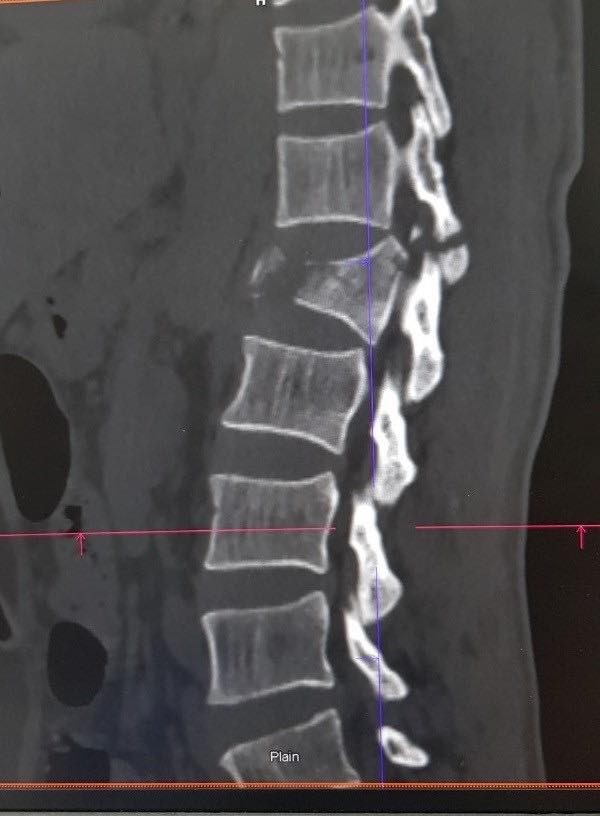

Ảnh minh họa đoạn đốt sống L1 trên cơ thể